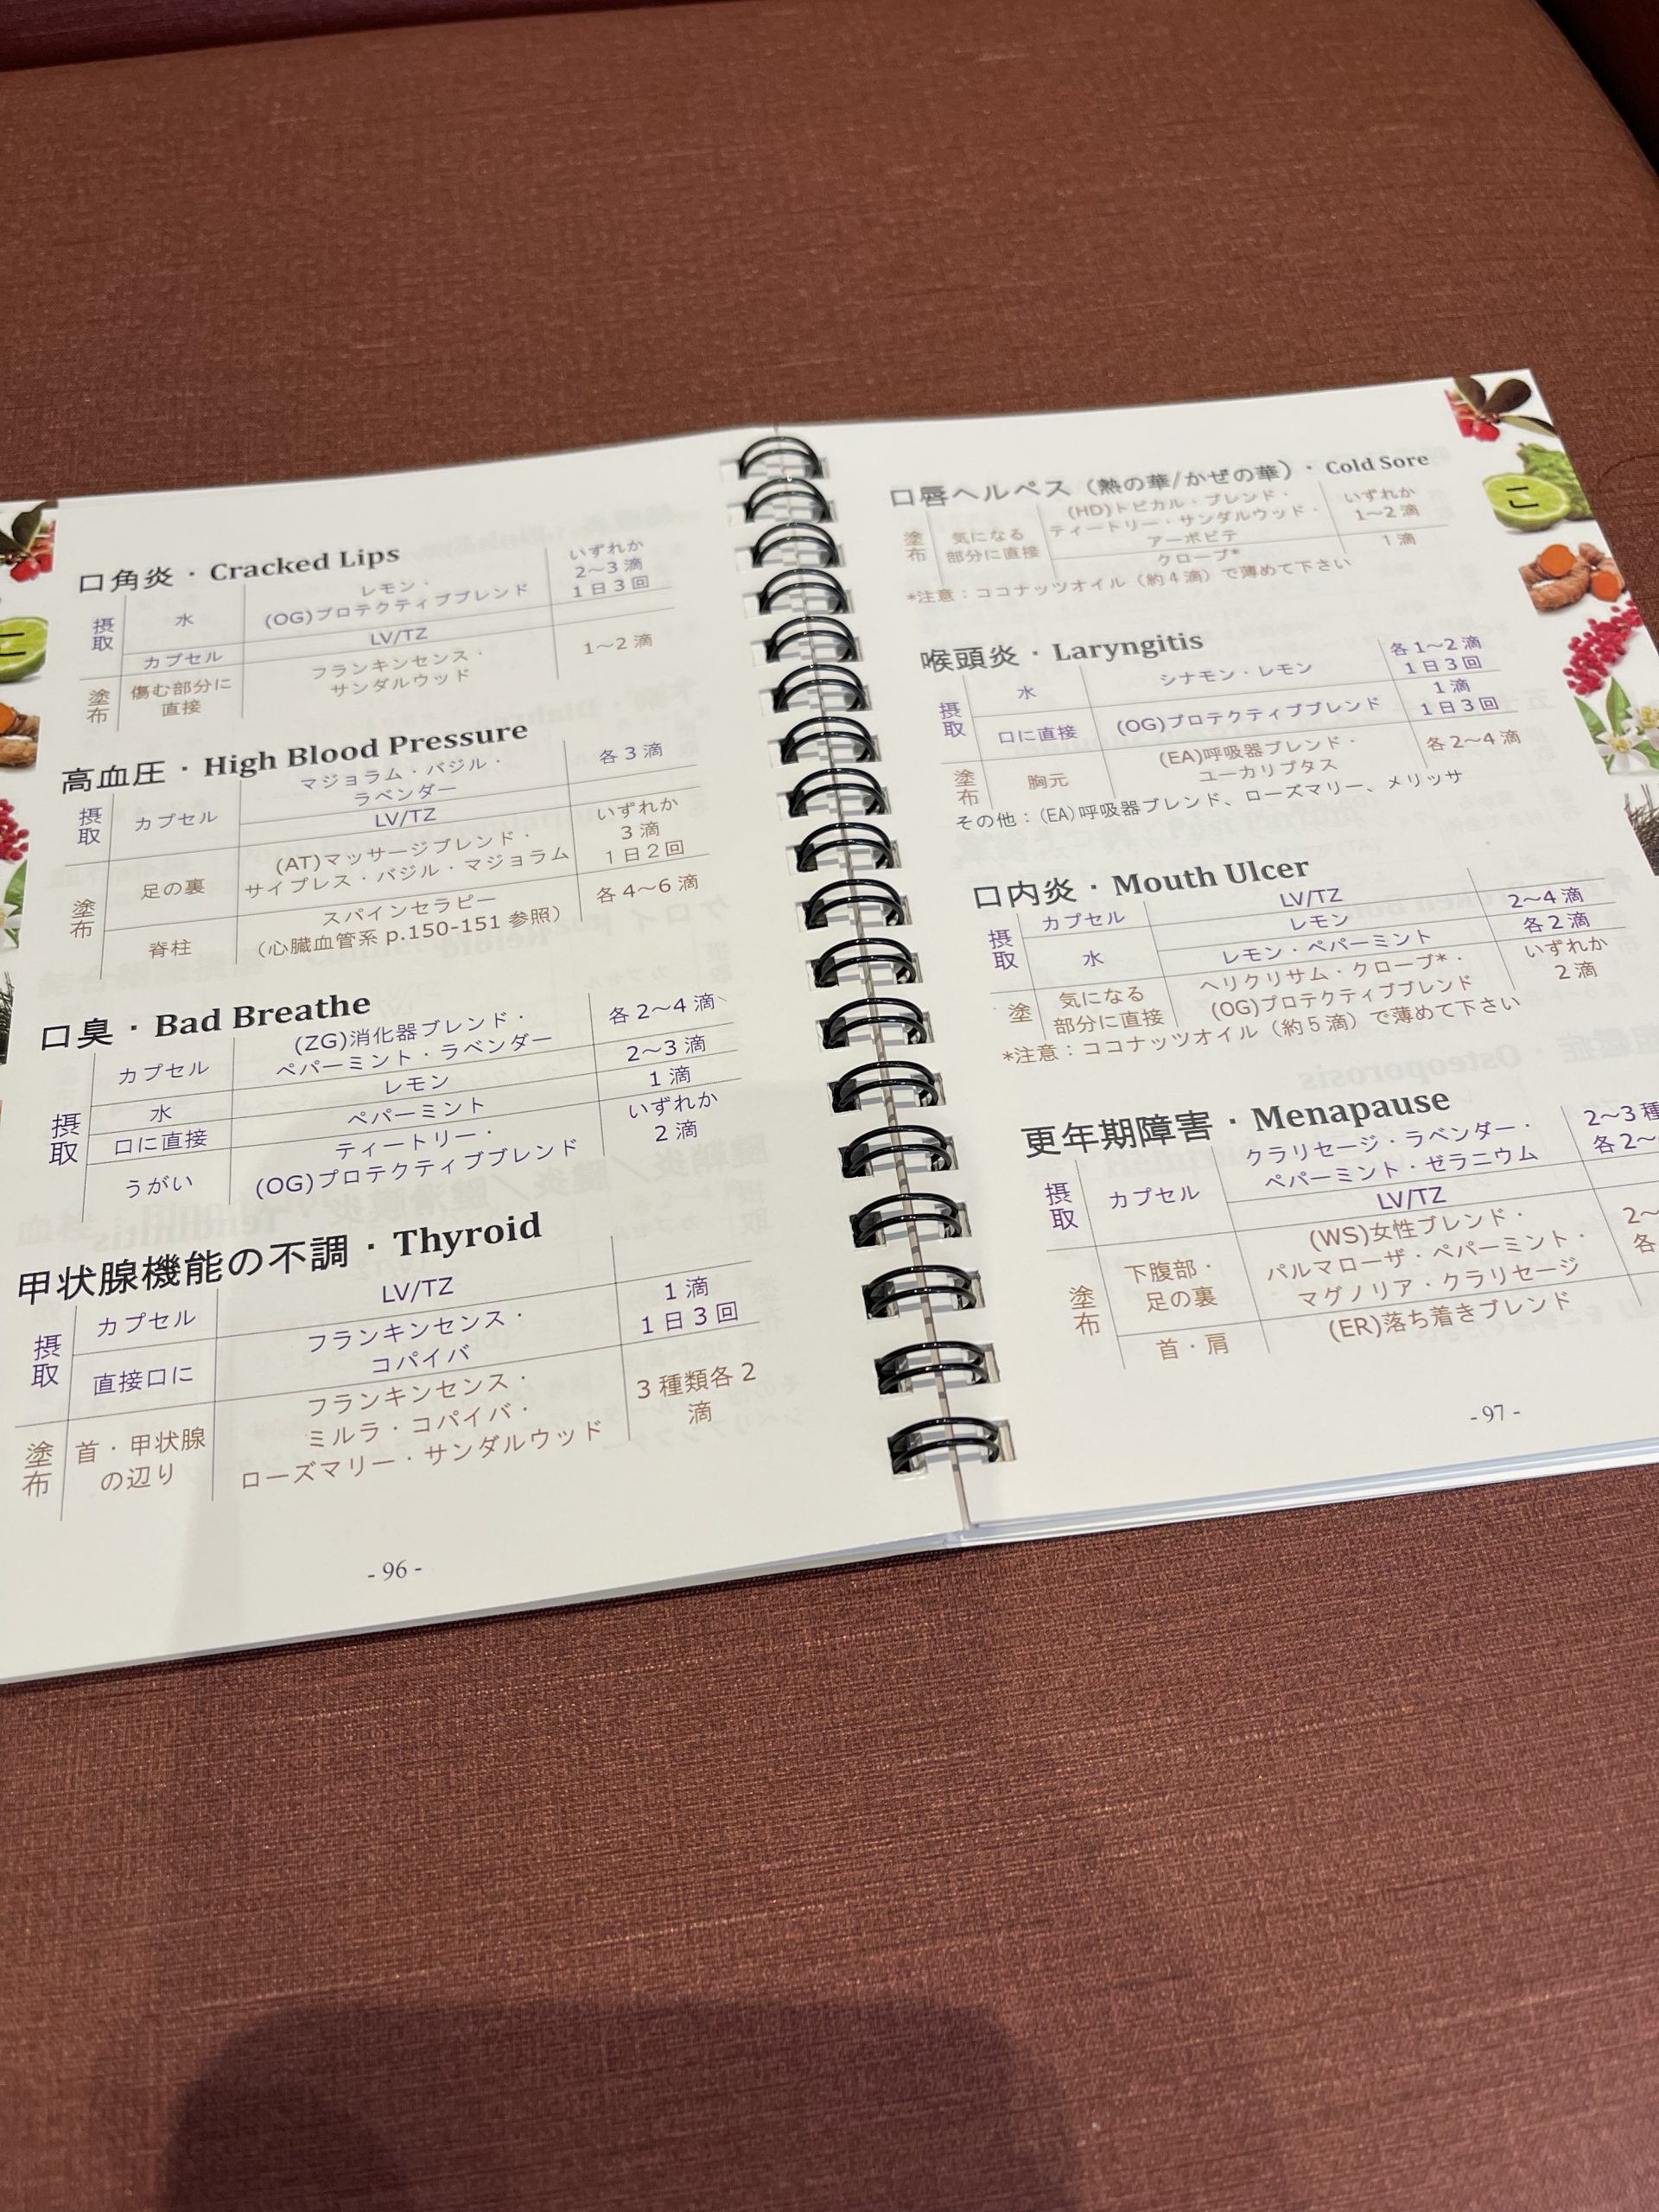

メディカルアロマ外来 2022.3.1

医療に使われるアロマを取り入れております。

クリニックで取り扱っているアロマオイルはドテラ社のものでCPTG基準を満たした最高級の品質です。

経口摂取もできますし原液塗布もできます。